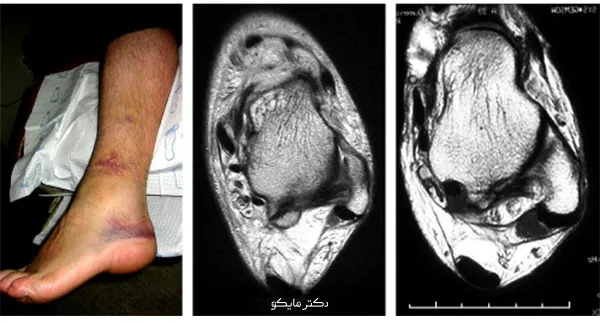

عکس پیچ خوردگی مچ پا

در این تصویر می توانید ام آر آی مچ بعد از پیچ خوردگی پا را ببینید.